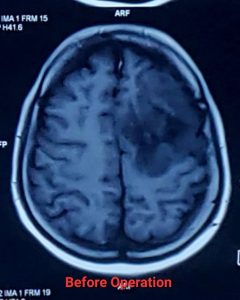

লো-গ্রেড গ্লিওমা (Low-Grade Glioma - LGG)

লো-গ্রেড গ্লিওমা (Low-Grade Glioma – LGG) হলো মস্তিষ্কের টিউমার যা মস্তিষ্কের সহায়ক কোষ (গ্লিয়াল সেল) থেকে তৈরি হয়। এগুলি সাধারণত ধীর গতিতে বৃদ্ধি পায়, তবে সময়ের সাথে সাথে এগুলি আরও আগ্রাসী (উচ্চ-গ্রেডের) হতে পারে। সার্জারি লো-গ্রেড গ্লিওমার চিকিৎসার একটি গুরুত্বপূর্ণ অংশ।

* সর্বাধিক সম্ভব টিউমার অপসারণ (Maximal Safe Resection): নিউরোসার্জনরা যতটা সম্ভব টিউমারের অংশ অপসারণ করার চেষ্টা করেন, যাতে মস্তিষ্কের গুরুত্বপূর্ণ কার্যকারিতার (যেমন – কথা বলা, নড়াচড়া, স্মৃতিশক্তি) ক্ষতি না হয়। কিছু ক্ষেত্রে, সম্পূর্ণ টিউমার অপসারণ সম্ভব না হলেও, আংশিক অপসারণও রোগের অগ্রগতি ধীর করতে এবং লক্ষণগুলি কমাতে সাহায্য করতে পারে।

* নিউরোনেভিগেশন (Neuronavigation) এবং ফাংশনাল এমআরআই (Functional MRI – fMRI): সার্জারির আগে fMRI এবং ডিটিআই (DTI) ম্যাপিং ব্যবহার করে মস্তিষ্কের কোন অংশগুলি গুরুত্বপূর্ণ কার্যকারিতা নিয়ন্ত্রণ করে তা চিহ্নিত করা হয়। নিউরোনেভিগেশন সার্জনের জন্য রিয়েল-টাইম গাইডেন্স প্রদান করে, যা টিউমার অপসারণে নির্ভুলতা বাড়ায়।

লো-গ্রেড গ্লিওমা সার্জারির পর prognosis বেশ ভালো হতে পারে, বিশেষ করে যদি টিউমার সম্পূর্ণ বা বেশিরভাগ অংশ অপসারণ করা যায়। গবেষণায় দেখা গেছে, দ্রুত এবং কার্যকরী সার্জারি জীবনকাল বাড়াতে এবং খিঁচুনি নিয়ন্ত্রণে আনতে সাহায্য করে। যদিও লো-গ্রেড গ্লিওমা সাধারণত ধীর গতিতে বৃদ্ধি পায়, তবুও এটি সময়ের সাথে সাথে উচ্চ-গ্রেডে পরিবর্তিত হতে পারে। তাই নিয়মিত ফলো-আপ এবং প্রয়োজনে অন্যান্য চিকিৎসা,যেমন – রেডিয়েশন থেরাপি বা কেমোথেরাপি, অত্যন্ত গুরুত্বপূর্ণ।